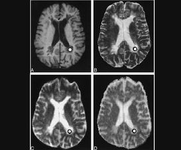

在2016年美国神经病学会年会上,来自梅奥诊所的Catherine Chong发表了数个关于偏头痛的研究,此前Chong一直致力于研究偏头痛患者的功能性MRI及解剖结构。美国医景(Medscape)网站的记者针对这一问题对Chong进行了采访。